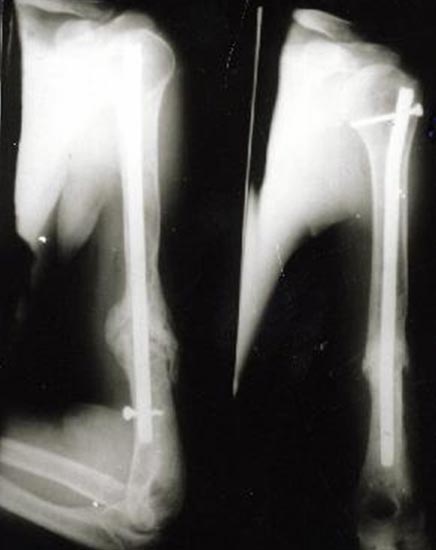

病例二、患者女性,20岁,肱骨中段骨折1年,骨不连形成。

带锁髓内钉固定骨折端提供支撑力,患者自体骨髓细胞经与松质骨和骨生长因子复合,

使没有细胞的植骨材料变成了有细胞的活骨。骨折在8个月后愈合。

手术后去除内固定